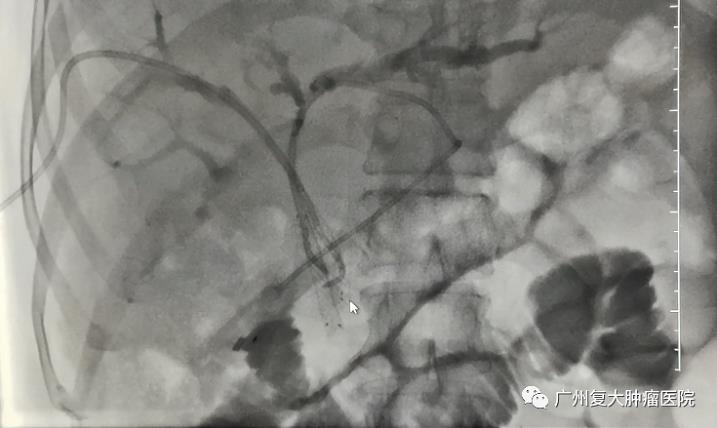

但患者之前在外院放置的内外引流管导致他出现发烧、寒颤、呼吸困难、胆道感染……在我院经过内科治疗后得到缓解。而接下来的治疗就是将内外引流管转成内引流,即置入支架,拔掉外引流,这样才能尽可能保留肝功能,为后续抗肿瘤治疗提供有力的保障。

“专家们多次研究后说我这个情况,可以用支架把狭窄的胆道支撑起来,疏通胆管。”但是支架只放一侧引流不充分,之后另一侧也没有机会再放支架,最好是同时放两个支架,但这个风险又太大。“我当时最多有4根引流管,4个引流袋,每一次呼吸都很困难,我总觉得自己活不了几天。”人们总说男儿有泪不轻弹,但他自己也悄悄哭过几次,他觉得自己很快就要跟亲朋好友说再见。“我想开车找个地方待着,不想治疗了,但是我爱人不肯放弃。”

在爱人的坚持下,在经过多次沟通讲解后,邹叔叔最终同意接受Y型胆道支架置入术,所幸的是,过程顺利,胆道引流通畅,他的胆红素以及胆道感染也得到了很好的控制。“术后徐院长告诉我,这个支架置入风险极高,成功率只有20%。”邹叔叔很庆幸,也感谢爱人的坚持和医生精湛的医技。